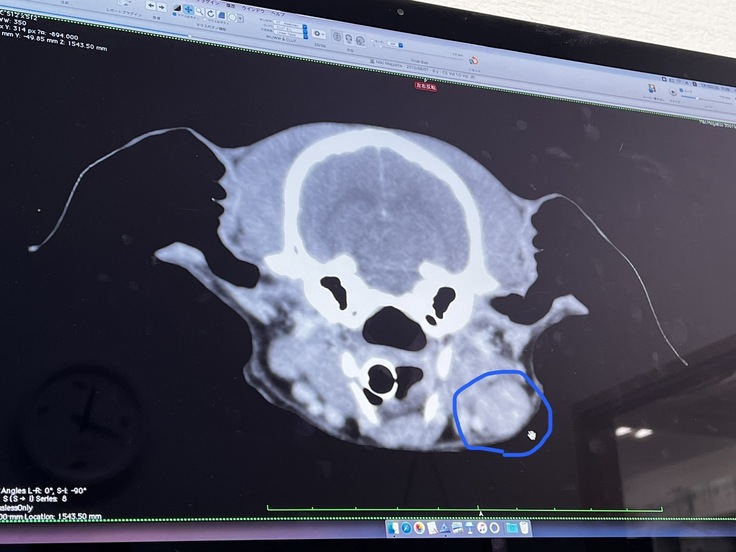

まだ CTの画像をいただけていないので こちらに 掲載できませんが

口腔内にいる 灰色の陰(鼻の骨の方に広がっています)

下顎のリンパ節の腫れ イヤな予感は的中でした。

CTの結果として

左顎下部分のリンパ節へ転移と